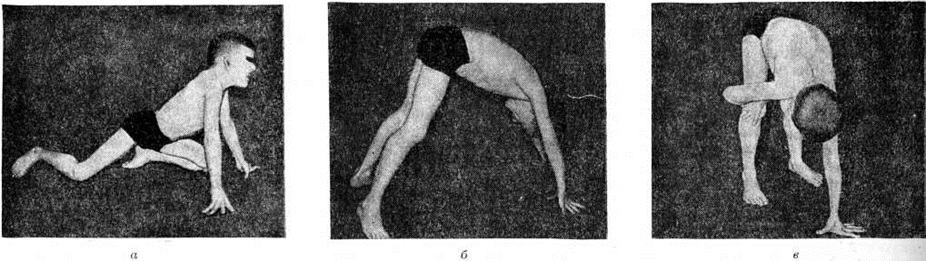

Поражение поперечнополосатых мышц глаз приводит к частичной или полной офтальмоплегии, птозу, экзофтальму, лагофтальму. Поражение мышц мягкого неба, глотки и гортани проявляется нарушением глотания и фонации. Симптомы поражения мышц плечевого пояса — ограничение объёма активных движений в проксимальных отделах рук, отставание лопаток от туловища — симптом «крыловидных лопаток» (рисунок 4), отсутствие сопротивления мышц плечевого пояса при поднимании больного за подмышки — симптом «свободных надплечий» (рисунок 5.); плечи больного поднимаются вверх, а голова как бы проваливается между ними. Атрофия длинных мышц спины и тазового пояса проявляется нарушением осанки и походки: выражен гипер лордоз позвоночника, голова несколько запрокинута назад, туловище при ходьбе ритмично раскачивается — «утиная походка». Затруднено поднимание по лестнице, вставание из сидячего положения. Для того чтобы принять вертикальное положение, больной вынужден прибегать к помощи рук, опираясь на соседние предметы или собственные бедра,— вставание «лесенкой» (симптом «лестницы» — рисунок 6, я, б, в). При атрофии косых мышц живота наблюдается симптом «осиной талии». Нарушение походки по типу «степпажа» или «петушиной походки» характерно для локализации миодистрофического процесса в мышцах голени и стопы. Поражение мышц приводит к ограничению подвижности суставов вплоть до образования контрактур. Присоединяющаяся, как правило, в поздней стадии заболевания легочно-сердечная недостаточность является следствием миодистрофического процесса в миокарде и дыхательной мускулатуре. При электромиографическом исследовании выявляют снижение амплитуды осцилляций, высокую частоту полифазных потенциалов, укорочение времени отдельных осцилляций.

Рис. 6. | ||